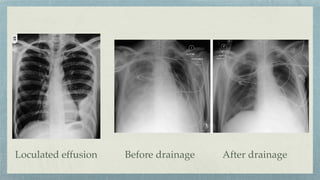

Pleural effusion

Large amount of

fl

uid is displaced in supine

No meniscus, only veil like opacity

Types:-

Lamellar- Linear opacity, paralleling lung surface

Encysted- Loculation within a

fi

ssure

Subpulmomary- Pooling within the pleural surface

below the lung

Meniscus Sign Subpulmonic effusion

Loculated effusion Before drainage After drainage